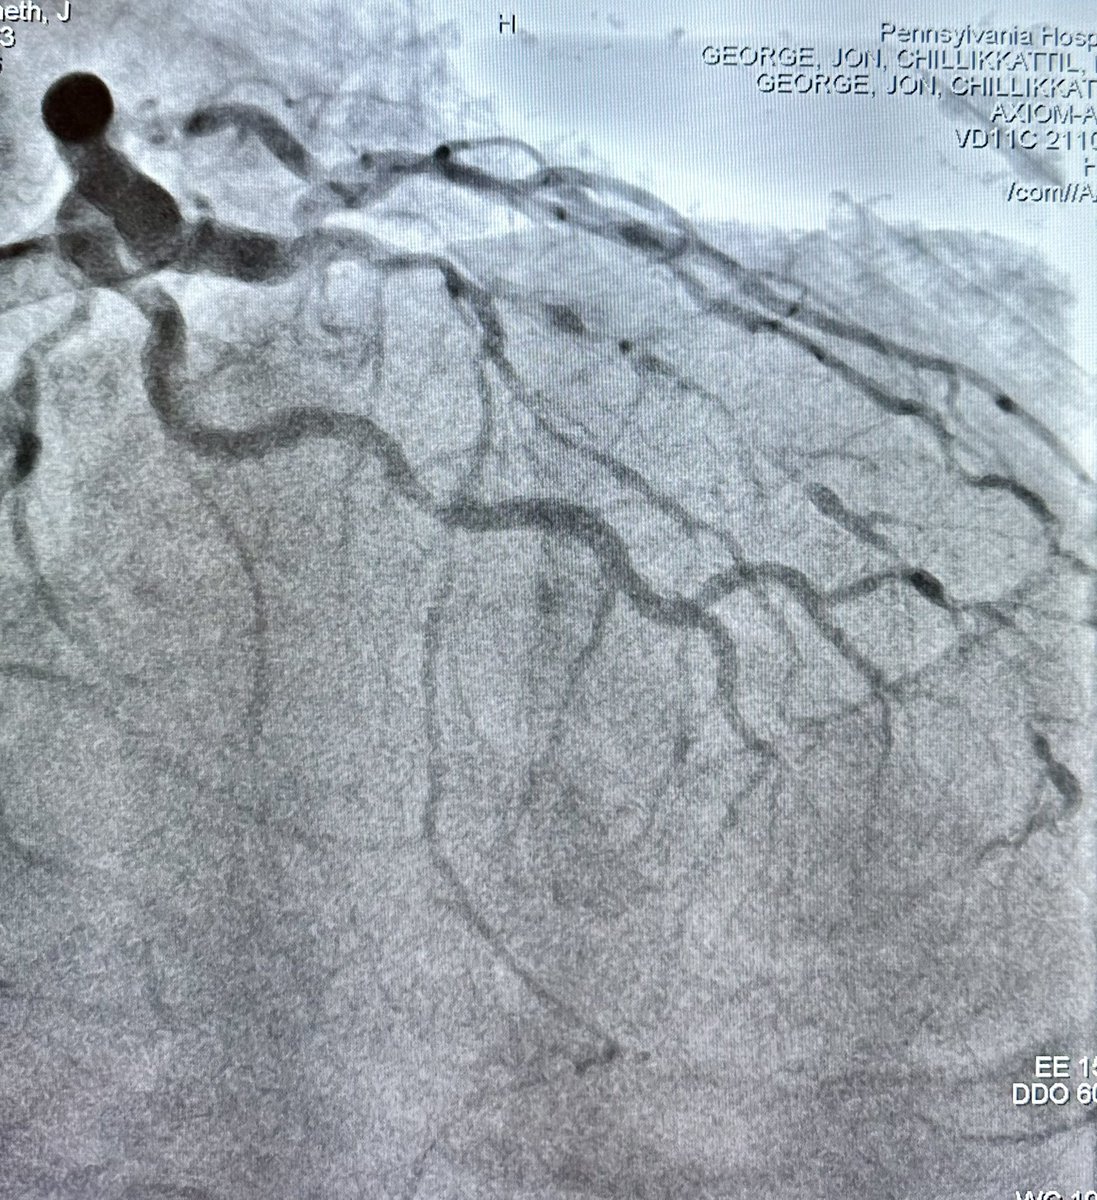

#CTOPCI at #PennsyInterventions: failed prior PCI LAD due to heavy calcification successfully crossed with initial subintimal dissection into septal and dual lumen #Sasuke catheter assisted re-entry into the true distal LAD! Combined case win with @vvarghesedo @ReVascMed